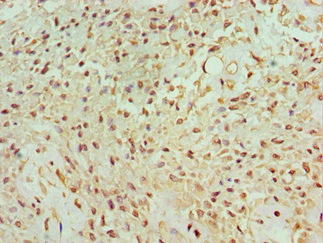

Immunohistochemistry of paraffin-embedded human breast cancer using CSB-PA854079ESR1HU at dilution of 1:100